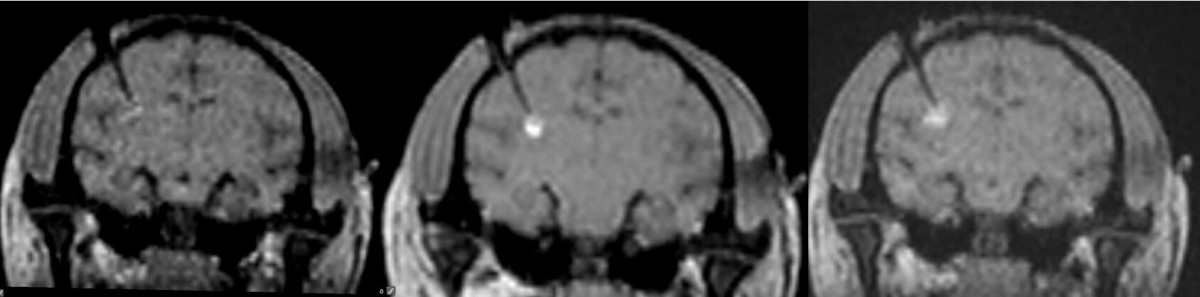

不同治疗组的食蟹猴壳核中STEM121表达的差异,可以评估细胞移植的疗效和细胞存活的持久性。(A):接受载体治疗7天的猴子(V7-1)的冠状脑切片,经过STEM121免疫染色和尼氏复染。(B):接受细胞治疗7天的猴子(C7-2)的冠状脑切片,经过STEM121免疫染色和尼氏复染。(C):接受细胞治疗30天的猴子(C30-1)的冠状脑切片,经过STEM121免疫染色和尼氏复染。(a),(b)和(c):分别对应(A),(B)和(C)中方框区域的更高放大倍数图像,更清晰地展示了STEM121阳性细胞和纤维的分布。黑色箭头:指向STEM121阳性纤维。

不同治疗组的食蟹猴壳核中STEM121表达的差异,可以评估细胞移植的疗效和细胞存活的持久性。(A):接受载体治疗7天的猴子(V7-1)的冠状脑切片,经过STEM121免疫染色和尼氏复染。(B):接受细胞治疗7天的猴子(C7-2)的冠状脑切片,经过STEM121免疫染色和尼氏复染。(C):接受细胞治疗30天的猴子(C30-1)的冠状脑切片,经过STEM121免疫染色和尼氏复染。(a),(b)和(c):分别对应(A),(B)和(C)中方框区域的更高放大倍数图像,更清晰地展示了STEM121阳性细胞和纤维的分布。黑色箭头:指向STEM121阳性纤维。创新与意义